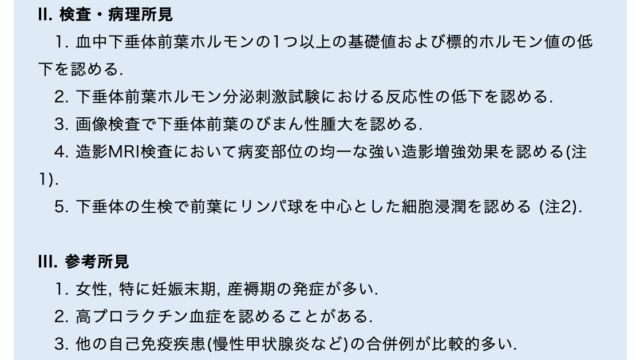

診断基準

神戸大学のグループが提唱している診断基準は

①後天的なGH・PRL・TSHの特異的な欠乏

内分泌学的所見では、GH・PRLが検出下限以下で、TSH・IGF-1・fT4が低値を示す。

負荷試験でこれらのホルモンの反応が悪い。

他の下垂体ホルモンの分泌の障害がない。

下垂体MRIでは明らかな異常が認められないため、原因不明の中枢性甲状腺機能低下症と診断されることが多い。しかし、造影MRIを行うと一部の患者では不均一な増強を伴うわずかに萎縮した下垂体前葉が認められる。

橋本病や1型糖尿病などの自己免疫疾患を合併する例もある。

②抗PIT-1抗体やPIT-1反応性T細胞の存在

③胸腺腫や悪性腫瘍の合併

ほとんどの患者は、胸腺腫や悪性腫瘍を合併している。

一般に、内分泌学的異常が悪性腫瘍の診断に先行する。

Probable:診断基準①を満たす

Definite:診断基準①と②を満たす

注釈:診断基準③は診断の助けとなるが、内分泌学的異常の診断時には必ずしも明らかではない。